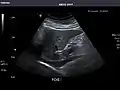

Gallbladder

Gallbladder: No stones, wall thickening, or pericholecystic fluid.